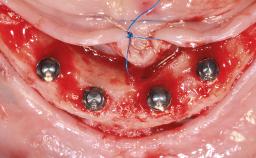

Single Midline Implant in the Edentulous Mandible Without Augmentation

| Number of implants | One |

| Number of implants | One |